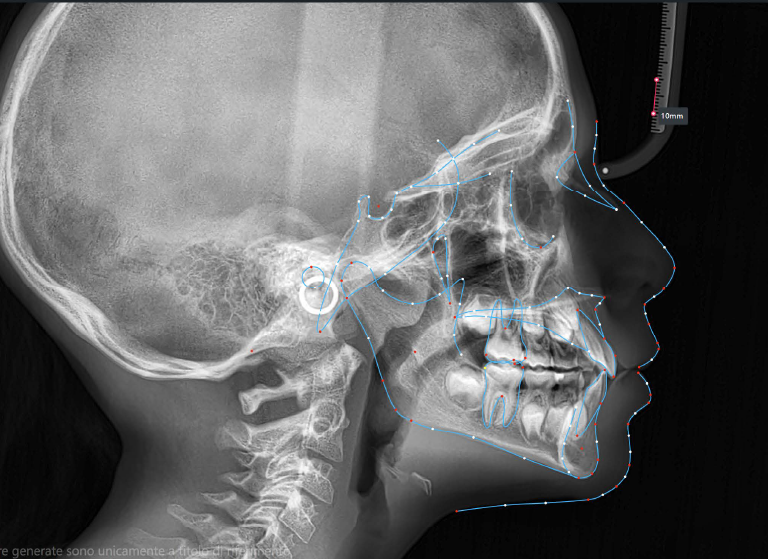

The patient presented with a skeletal Class I relationship and a mesofacial growth pattern, indicating balanced sagittal and vertical skeletal proportions. Dental examination revealed a Class I molar and canine relationship bilaterally. The patient was in the mixed dentition phase. Significant dental crowding was observed in both arches, consistent with a dentoalveolar discrepancy. Midline deviations were present, affecting dental symmetry and occlusal harmony. The maxillary lateral incisors were in crossbite, contributing to anterior transverse discrepancy and functional imbalance.

Periodontal evaluation revealed early signs of periodontal disease, primarily affecting tooth 41. Radiographic assessment demonstrated root convergence of teeth 11 and 21, indicating compromised root parallelism. Overall, the initial presentation was characterized by dentoalveolar crowding, transverse discrepancies, occlusal asymmetries, and early periodontal involvement within an otherwise favorable skeletal framework, requiring a carefully planned orthodontic approach to ensure functional stability and periodontal preservation.